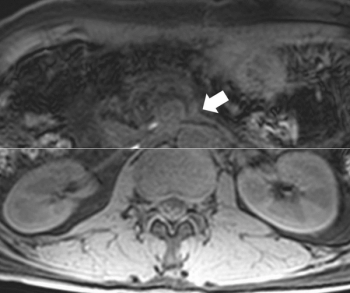

What is the diagnosis?